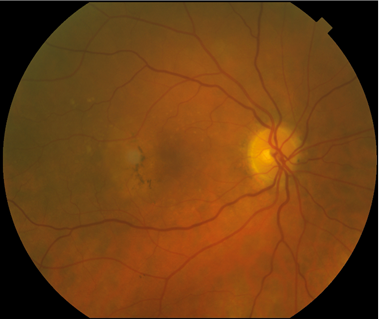

FUNDUS DESCRIPTION: |

OD OS |

OS Red-Free: Venous: Recirc: Late:

Impression